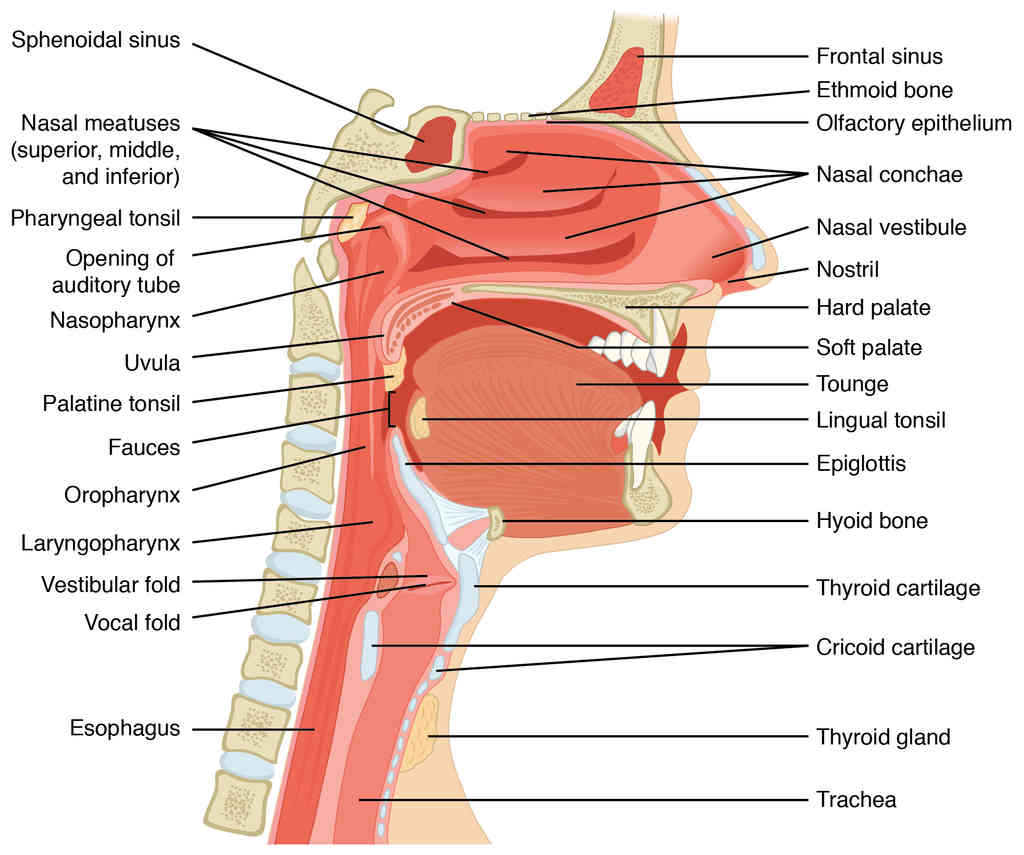

This page is under construction. For now, it is just a resource of the images found in the OpenStax Anatomy and Physiology Handbook. It wil slowly change into a revision tool. Each slide has a number. Use this to refer to the slide. When completed, it will have an unlabelled section, with labelled slides in parallel. On the unlabelled slides, write your answer and use the labelled slide to assess yourself. Keep track by also noting the number on each slide. Improvement at each attempt is important, more so than full marks on a first attempt.